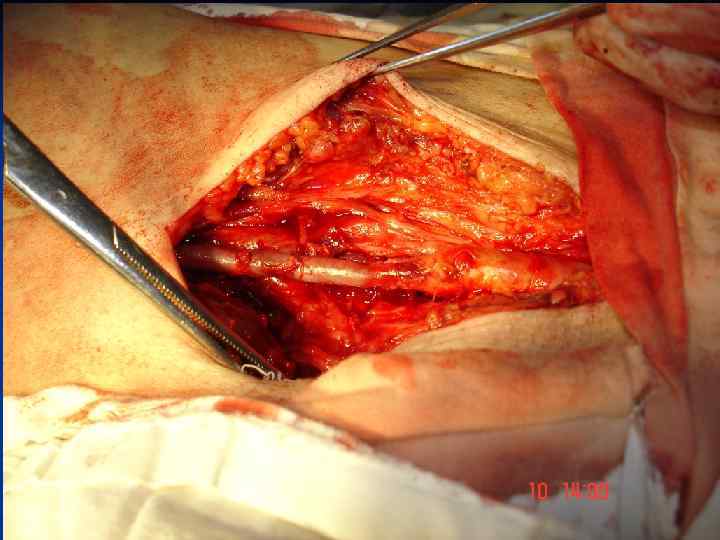

Стегно-підколінне аутовенозне протезування

Стегно-підколінне аутовенозне протезування